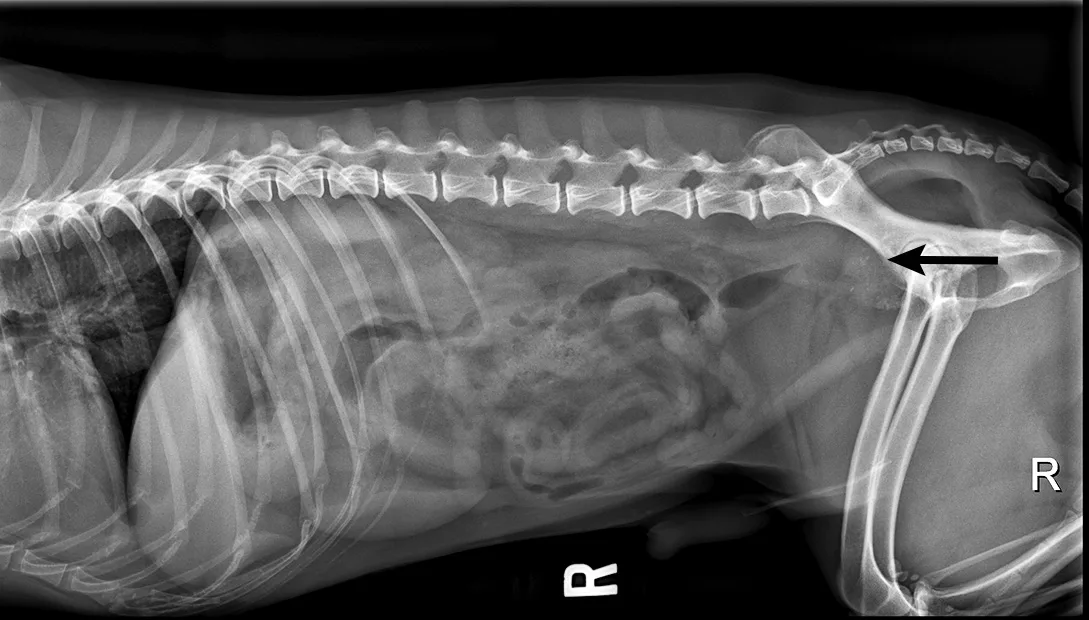

Other organs (eg, prostate in males) may be palpable depending on patient size. Intact males commonly have benign prostatic hypertrophy or bacterial prostatitis. Additional testing (eg, radiography, ultrasonography, urinalysis, urine culture) may be needed. As with transitional cell carcinoma, molecular tests can be submitted for diagnosis of prostatic carcinoma. DNA-based diagnostics are highly sensitive and specific, making these tests noninvasive and useful for diagnosis of transitional and prostatic carcinoma (Figure 3).12,13

Lateral abdominal radiograph of a dog.

FIGURE 3

Radiograph of an enlarged and mineralized prostate (arrow) in a dog diagnosed with prostatic carcinoma based on DNA urine testing. Image courtesy of Merrilee Holland, DVM, DACVR